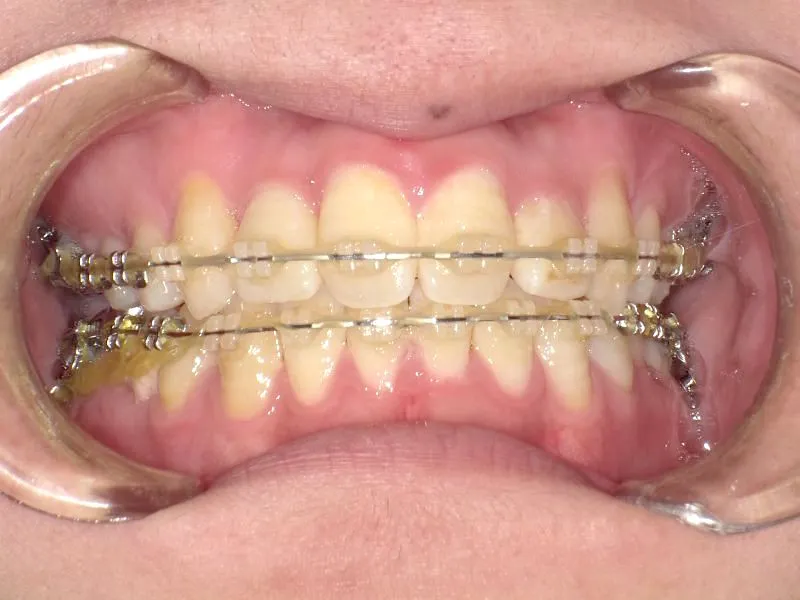

• 治療経過1

治療経過1